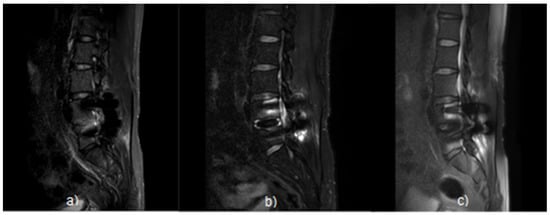

2.1. Subjects

2.2. Process of Producing Phantom

3.1. SNR Result of Pig L-Spine Phantom

3.2. SNR Result of Transplant Patients